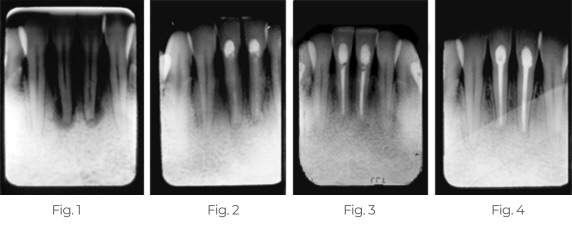

Behandlung von abszedierten Zähnen

Vier Monate nach einem Autounfall, bei dem das Kinn der Patientin auf das Lenkrad aufschlug, stellte sich die Patientin mit lockeren und schmerzhaften unteren mittleren Schneidezähnen vor. Wir führten sofort Wurzelkanäle durch und setzten TempCanal in die Kanäle ein, um die Heilung zu stimulieren.

Abb. 1: Röntgenbild mit abszedierten Zähnen und erheblichem Knochenverlust.

Abb. 2: Sechs Monate nach der Wurzelkanalbehandlung mit TempCanal zeigt das Röntgenbild, dass sich der Knochen auffüllt und die Heilung voranschreitet.

Abb. 3: Ein Jahr nach der Behandlung mit Pulpdent Root Canal Sealer zeigt das Röntgenbild, dass die Heilung und der Verschluss mit Pulpdent® Root Canal Sealer voranschreiten.

Abb. 4: Dreizehn Jahre nach der endgültigen Füllung zeigt das Röntgenbild den Langzeiterfolg.